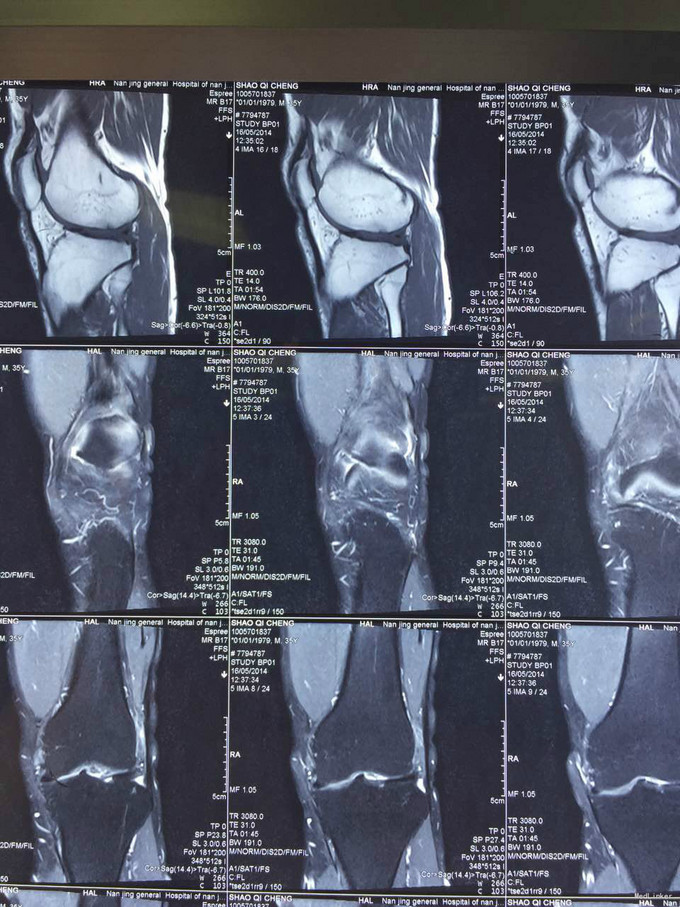

左膝扭伤后13年近1年反复不稳伴疼痛。 患者,男,39岁,13年前运动时扭伤左膝关节,当时未予重视,近1年出现左膝不稳伴疼痛,以上下楼、运动时明显,无法进行正常运动。遂于外院检查MRI(2015年3月)示:左膝关节退行性改变、左膝前交叉韧带信号异常、半月板信号异常、左膝关节内积液。为求进一步诊治来我门诊就诊,结合病史及体征,诊断“左膝半月板损伤、左膝前交叉韧带损伤”并收入院行进一步治疗。

入院诊断:左膝半月板损伤、左膝前交叉韧带损伤 治疗:入院后行左膝关节镜下外侧半月板成形+髁间窝成形+前交叉韧带自体肌腱重建手术。

随访:患者因为病程较长(十余年),术后3月膝关节才恢复正常活动度,行走正常。建议其术后1年再恢复正常运动。 讨论:该病例膝关节损伤时间较长,手术时关节已表现为提早退变(患者年龄并不大)。在前交叉韧带重建前,需要对其狭窄的髁间窝进行成形。术后恢复时间也较一般情况下延长。因此,建议关节出现病损应及时诊治。